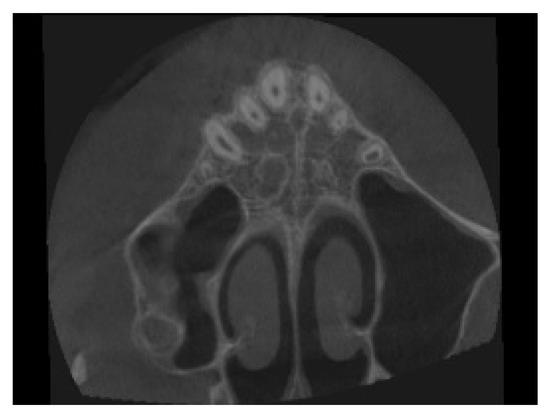

4. Case Report

4.1. Etiology and Diagnosis

4.4. Treatment Progress